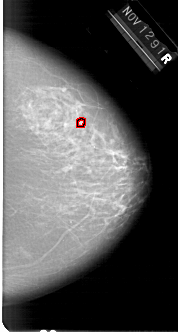

A_1648_1.RIGHT_CC

RIGHT_CC LINES 6301 PIXELS_PER_LINE 3376 BITS_PER_PIXEL 12 RESOLUTION 43.5 OVERLAY

FILE: A_1648_1.RIGHT_CC.OVERLAY

TOTAL_ABNORMALITIES 1

ABNORMALITY 1

LESION_TYPE CALCIFICATION TYPE PLEOMORPHIC DISTRIBUTION CLUSTERED

ASSESSMENT 4

SUBTLETY 2

PATHOLOGY BENIGN

TOTAL_OUTLINES 1

BOUNDARY